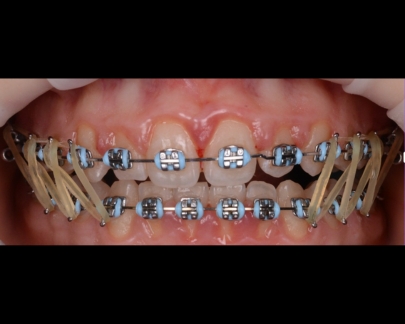

Sunt benzi elastice mici, din latex, folosite pentru corectarea mușcăturii și intercuspidarea dinților.

Elasticele se atașează de brackeții dinților superiori, respectiv inferiori și vin în diferite dimensiuni și grade de forță.

![]() | ![]() |

Elasticele ortodontice corectează raportul dintre maxilar și mandibulă (mușcătura). Sunt purtate conform indicațiilor medicului și sunt esențiale în multe tratamente pentru alinierea corectă a arcadelor.